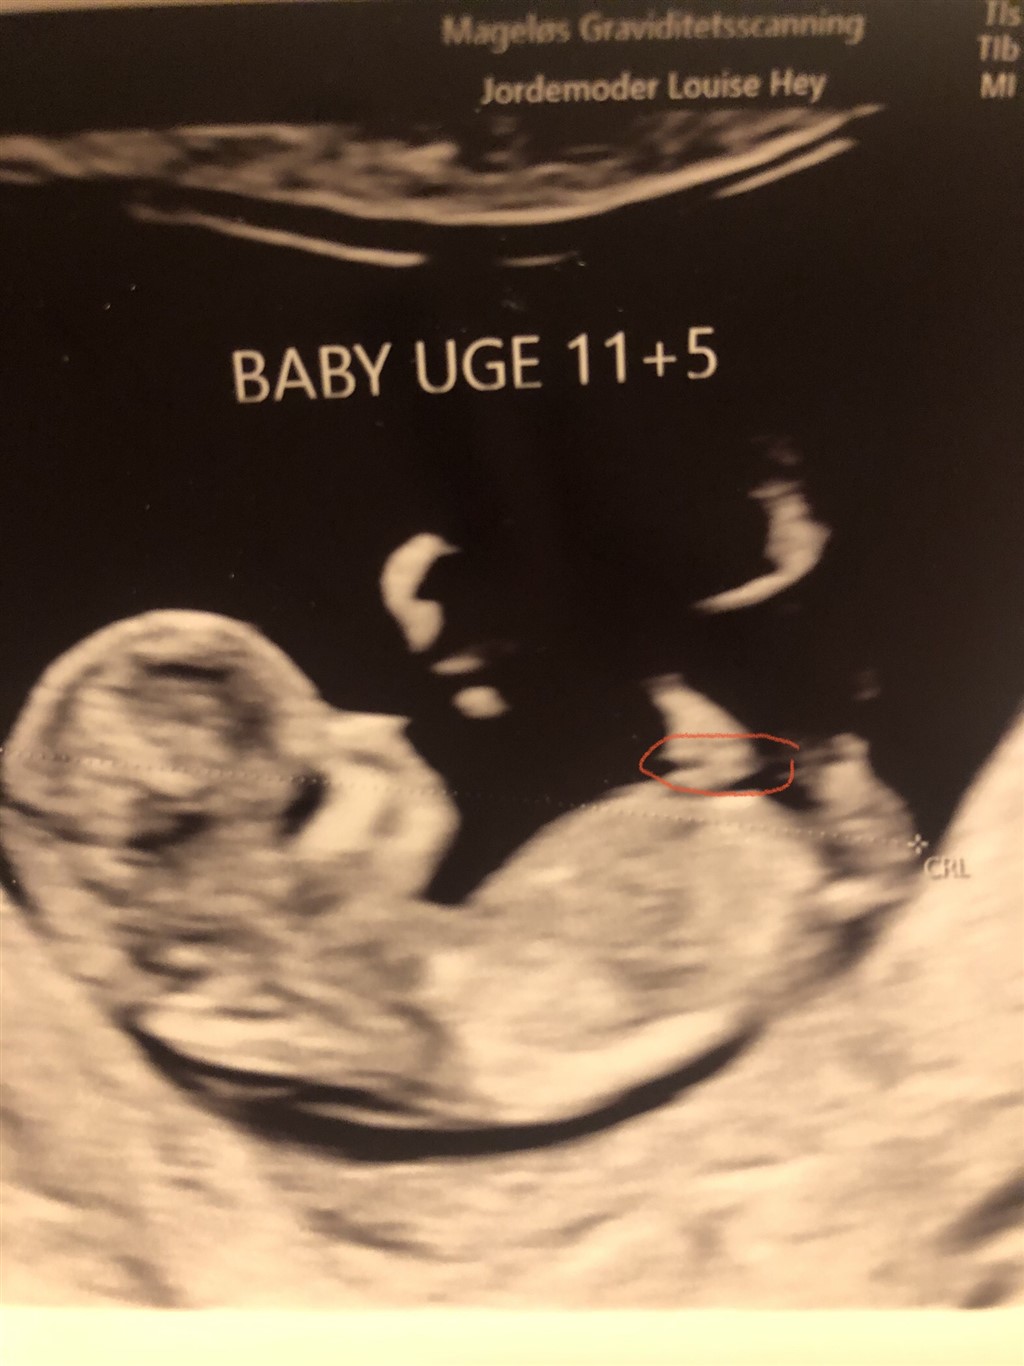

Det er for tidligt at vurdere køn, din babys Nub kan pt gå begge veje, så jeg tør ikke konkludere noget

Min dreng lignede en pige 13+1, hvor alle gættede pige og ingen på dreng - men til kønsscanning var nubben helt rejst, så derfor tør jeg ikke stole på noget så tidligt, hvis jeg var dig